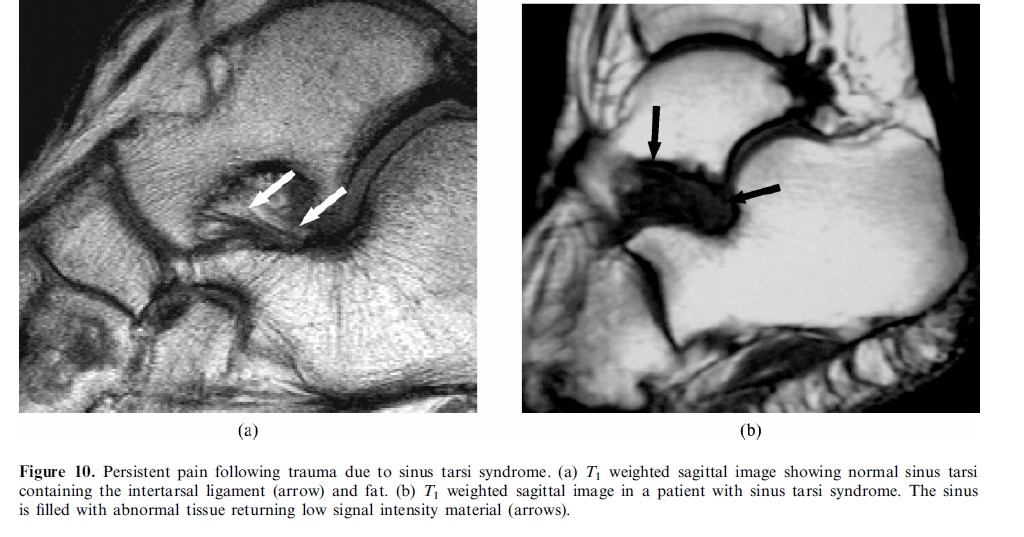

# MRI is the most suitable technique for global assessment of bone and soft tissues for persistent pain following injury.